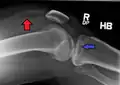

Lipohemarthrosis (presence of fat and blood from bone marrow in the joint space after an intraarticular fracture) seen on X-ray in a person with a subtle tibial plateau fracture

Lipohemarthrosis due to a tibial plateau fracture